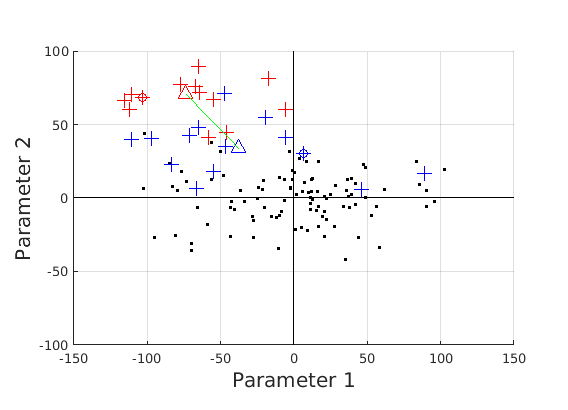

8 A case study of cranial profile model use for intervention outcome evaluation

In this section we take a sample of 25 boys, who are craniofacial craniosynostosis patients, 14 of which have undergone one type of corrective procedure (BS) and the other 11, another corrective procedure (TCR). Providing that the heads are sufficiently symmetrical and are amenable to ellipse fitting, we can parameterise all of these patients’ heads using our scale-normalised craniofacial profile model (2D model with face cropped out). We can then plot their pre-operative and post-operative parametrisations and compare them with the parameterisations of the 100 training examples. The expected result is that the parameterisations should show the head shapes moving nearer to the mean of the training examples. It also reveals which of the dominant modes of shape variation are most affected. The results are shown in figures 31 and 32.

For the BS patient set, the Mahalanobis distance of the mean pre-op parameters (red triangle in Fig. 31) is 4.670, and for the mean post-op parameters (blue triangle) is 2.302. For shape parameter 2 only these figures are 4.400 and 2.156.

It is not possible to make definitive statements relating to one method of intervention compared to another with these relatively small numbers of patients. However, the cranial profile model does show that both procedures on average, lead to a movement of head shape towards the mean of the training population. An example of analysis of intervention outcome for a BS patient is given in Fig. 33 and a TCR patient is given in Fig. 34. The particular example used is highlighted with circles on figures 31 and 32 to indicate pre-op and post-op parametrisations. To our knowledge this is the first use of statistical 3D craniofacial shape models in a clinical study.